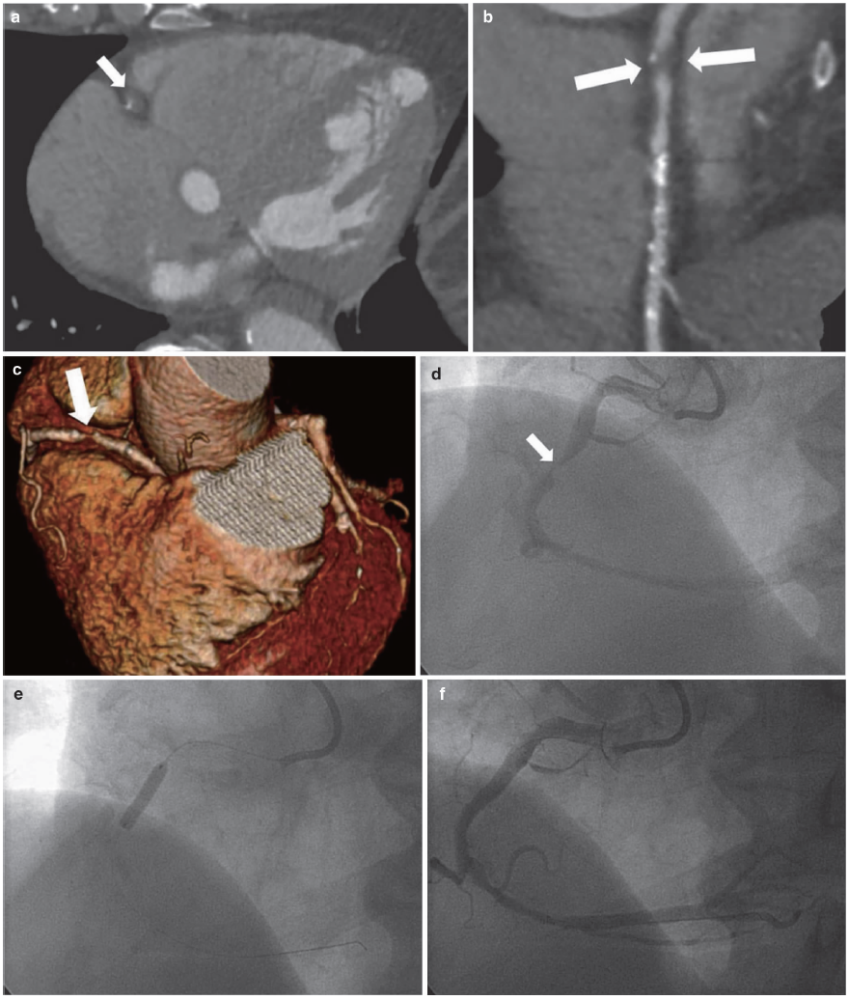

女,患者以"心慌气短"之主诉入我院心血管内科,临床诊断:冠状动脉粥样

冠状动脉cta常见伪影及对策汇总